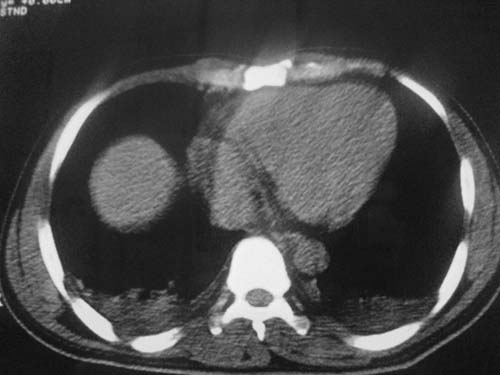

这是第五天拍的ct,纵隔窗我没都传,实在是太费时,请教各位老师,此病人有肺水肿吗?帮忙分析一下

支持肺水肿,双侧胸腔积液,入院第三天发病,会不会是心源性、药物过敏性、快速输液等情况,建议提供病史。

支持肺水肿,双侧胸腔积液.

入院第三天发病,会不会是心源性、药物过敏性、快速输液,栓塞,ards等情况,建议提供病史及患者转归情况。

患者第三天后逐渐加重,不符合肺挫伤表现,因为肺挫伤大部分是以外伤后24小时或36小时为发病高峰,之后就开始吸收。

1)双侧创伤性湿肺。2)双侧胸腔积液。